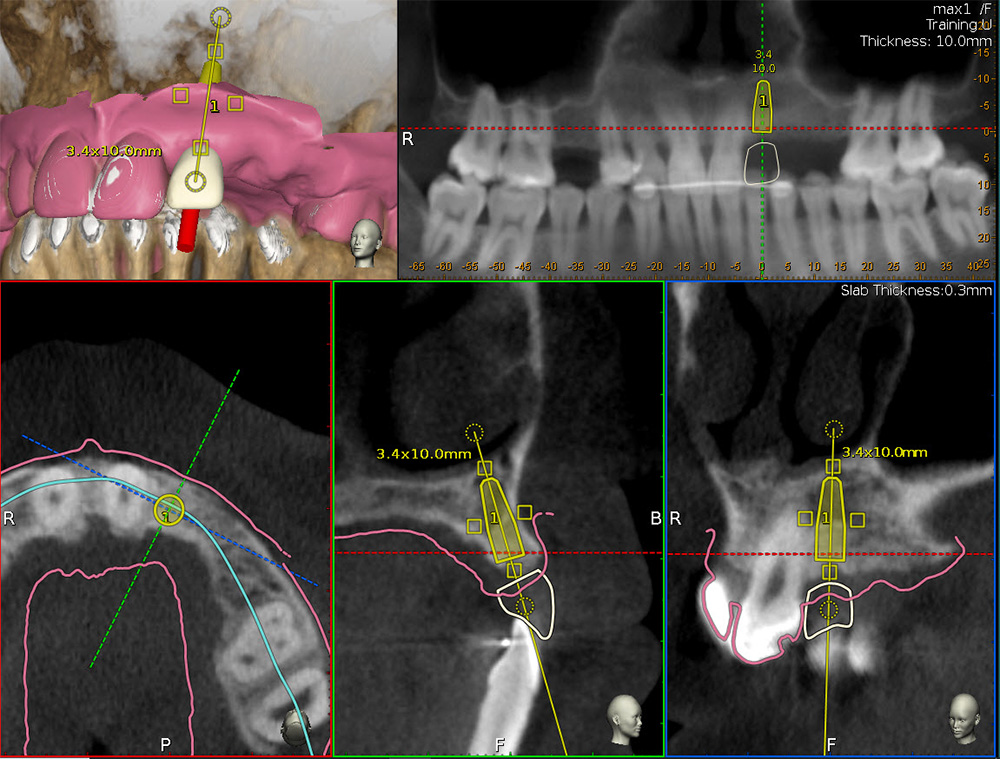

Implant dentistry demands precision placement of the fixture. Ideal location and position, dimension (length and diameter) and depth and angulation are mandated for positive treatment outcomes. Restoratively driven implant placement is paramount for the overall integrity of the dentition. Thus, it is essential to first visualize the final prosthesis in place in order to determine the type and number of implants necessary to support the intended prosthesis based on residual bone volume [Figures 1a, 1b].

Figure 1a

Figure 1b